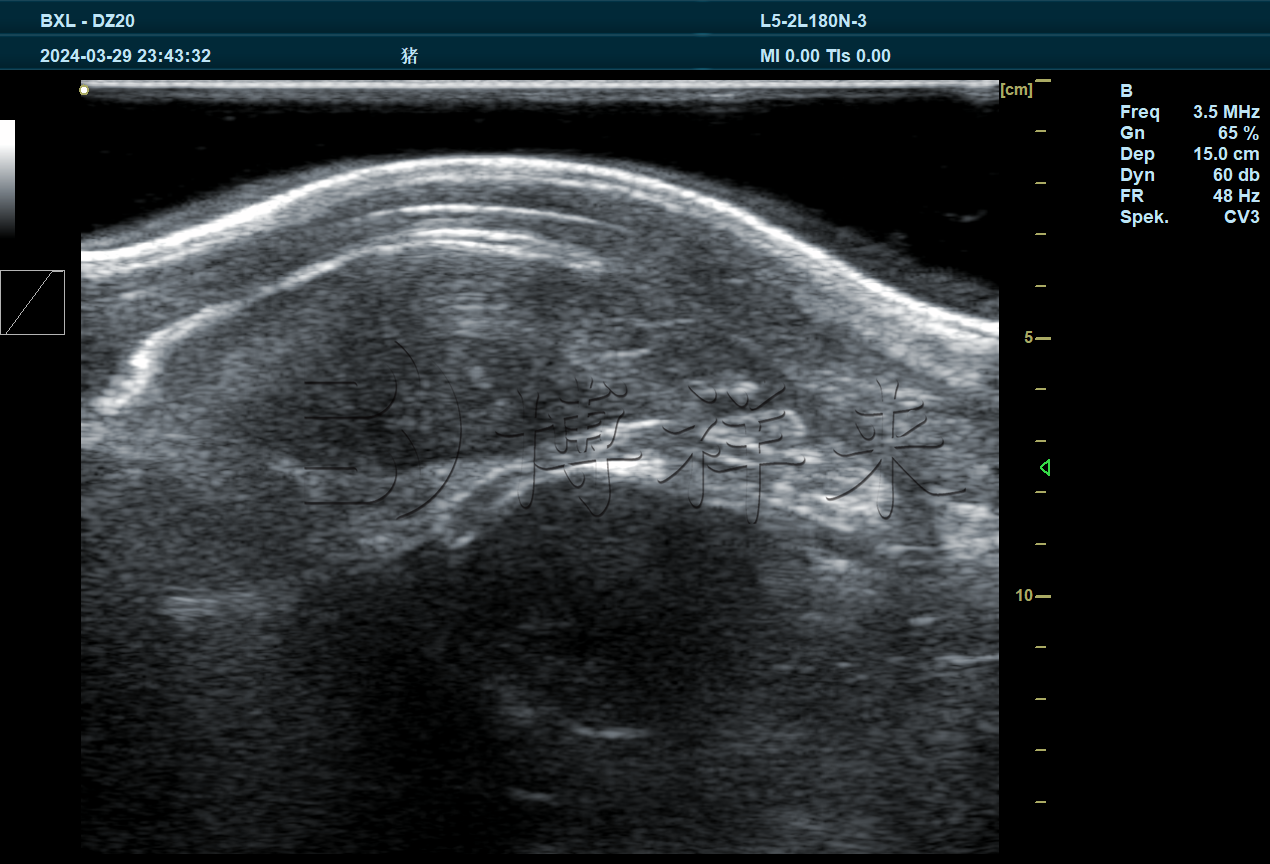

猪眼肌面积超声图像

• 眼肌面积分析:通过软件描绘眼肌轮廓并计算面积,反映出猪只肌肉发育水平。